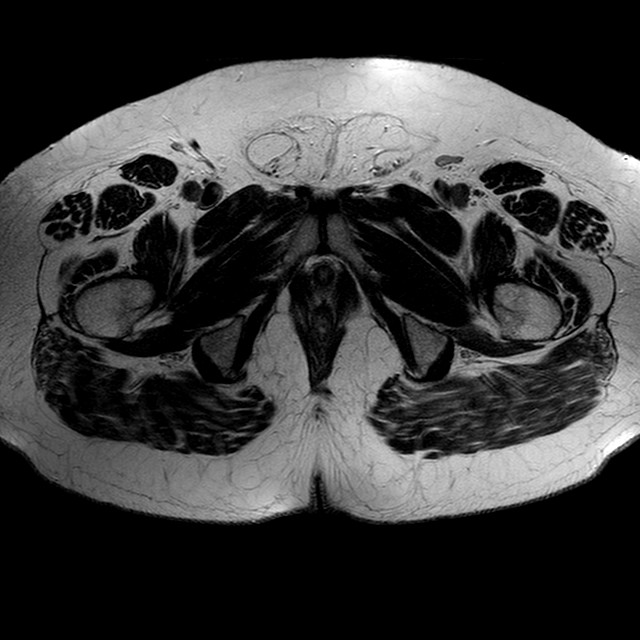

Esami: RMN BACINO

T2w TSE

Evidenti e simmetriche alterazioni osteofitosiche in regione coxo femorale con riduzione delle rime articolari. Degenerazione completa del cercine glenoideo. Non attuali segni di versamento articolare. Non segni di edema osseo che escludono attuale algodistrofia od osteonecrosi. Lieve e simmetrica riduzione del trofismo della muscolatura glutea.